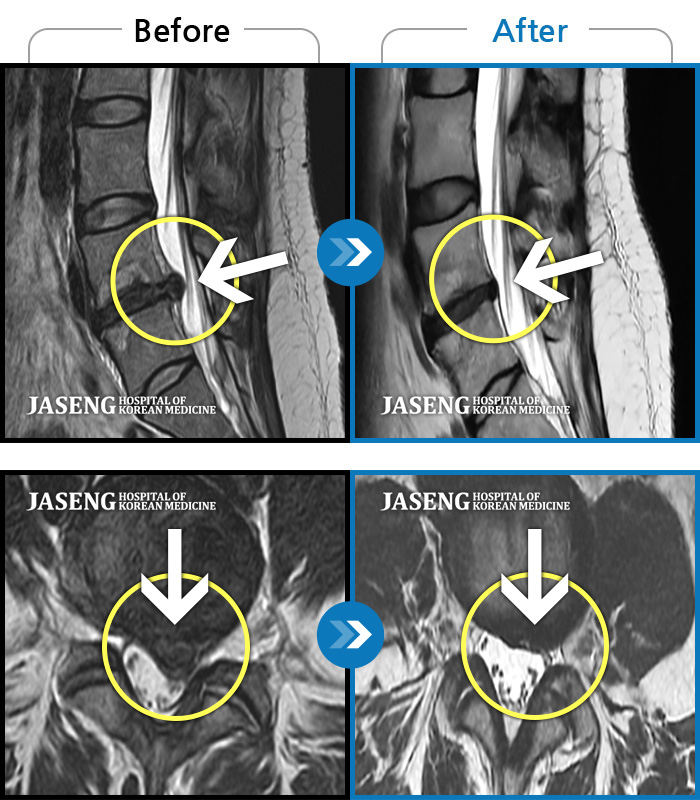

MRI 치료사례

처음 내원 시 좌측 허리 뻐근한 통증과 좌측 허벅지부터 발가락까지 이어지는 당기고 저린 증상으로 보행까지 불편감 호소하시며 내원하신 환자입니다.